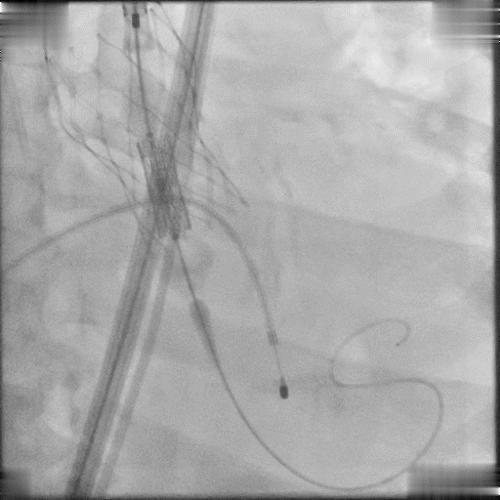

患者突发心脏停跳,紧急进行人工按压等急救措施;尝试予以冠脉保护,并在停跳状态下,快速植入Edwards Sapien 3球扩瓣;

尝试冠脉保护